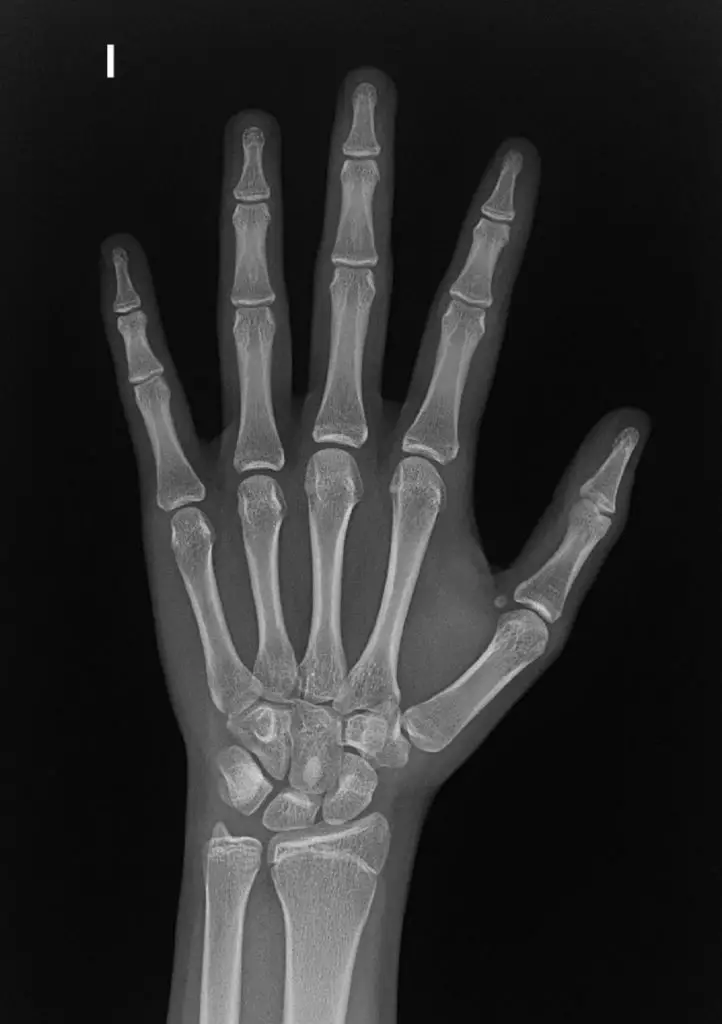

Con los rayos X es posible ver los huesos, lo cuales aparecerán de color blanco en la imagen; el aire, de color negro y los músculos y grasa, de color gris. Sin embargo, con ayuda de algunas sustancias químicas como bario o yodo, se pueden observar con mayor claridad algunas partes del cuerpo.

Puede determinar huesos rotos, dañados o con infecciones. En la misma línea se pueden ver el estado de las articulaciones, revelando artritis. También es posible encontrar la densidad de los huesos, conociendo si se tiene osteoporosis o problemas como cáncer de huesos. Asimismo, si se coloca en la mandíbula, se pueden encontrar caries.

- Radiografía de hueso.

- Radiografía de la mano.